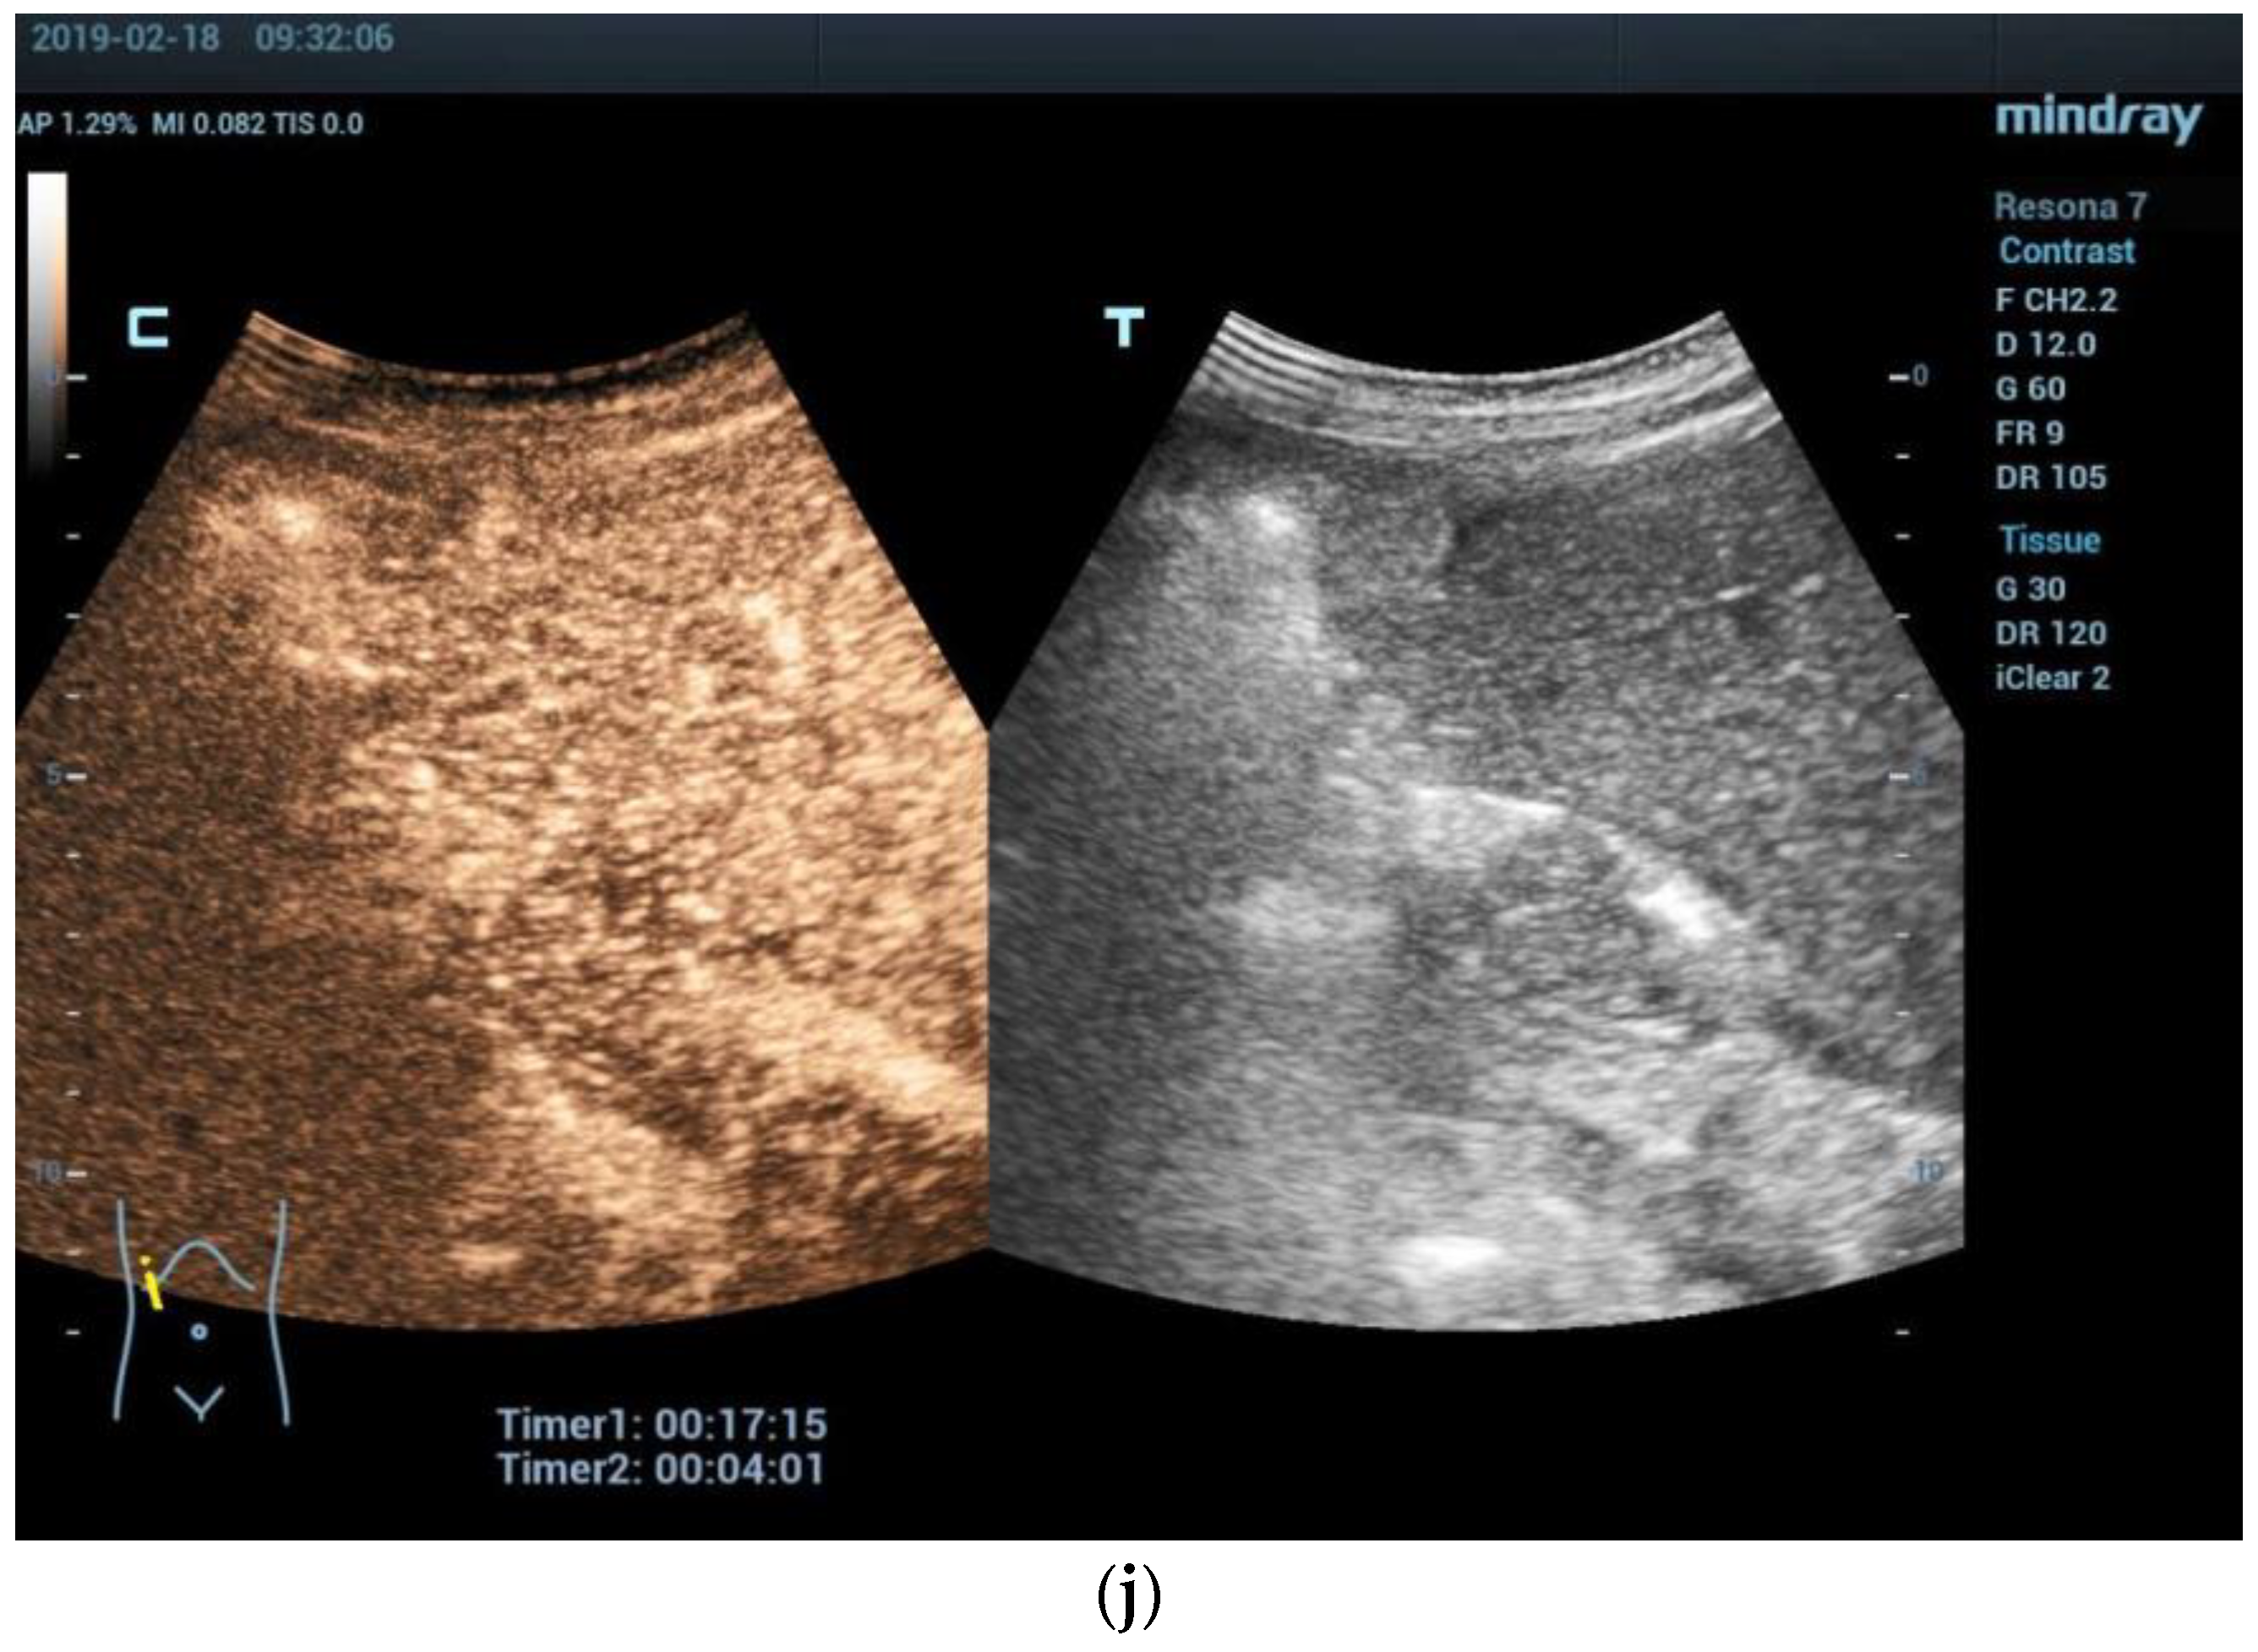

- Anupindi, S.A.; Biko, D.M.; Ntoulia, A.; Poznick, L.; Morgan, T.A.; Darge, K.; Back, S.J. Contrast-enhanced US Assessment of Focal Liver Lesions in Children. Radiographics 2017, 37, 1632–1647. [Google Scholar] [CrossRef]

- Wang, G.; Xie, X.; Chen, H.; Zhong, Z.; Zhou, W.; Jiang, H.; Xie, X.; Zhou, L. Development of a pediatric liver CEUS criterion to classify benign and malignant liver lesions in pediatric patients: A pilot study. Eur. Radiol. 2021, 31, 6747–6757. [Google Scholar] [CrossRef] [PubMed]

- McCarville, M.B. Contrast-enhanced sonography in pediatrics. Pediatr. Radiol. 2011, 41 (Suppl. S1), S238–S242. [Google Scholar] [CrossRef] [PubMed]

- Dong, Y.; Wang, W.P.; Mao, F.; Zhang, Q.; Yang, D.; Tannapfel, A.; Meloni, M.F.; Neye, H.; Clevert, D.A.; Dietrich, C.F. Imaging Features of Fibrolamellar Hepatocellular Carcinoma with Contrast-Enhanced Ultrasound. Ultraschall Der Med. 2021, 42, 306–313. [Google Scholar] [CrossRef] [PubMed]